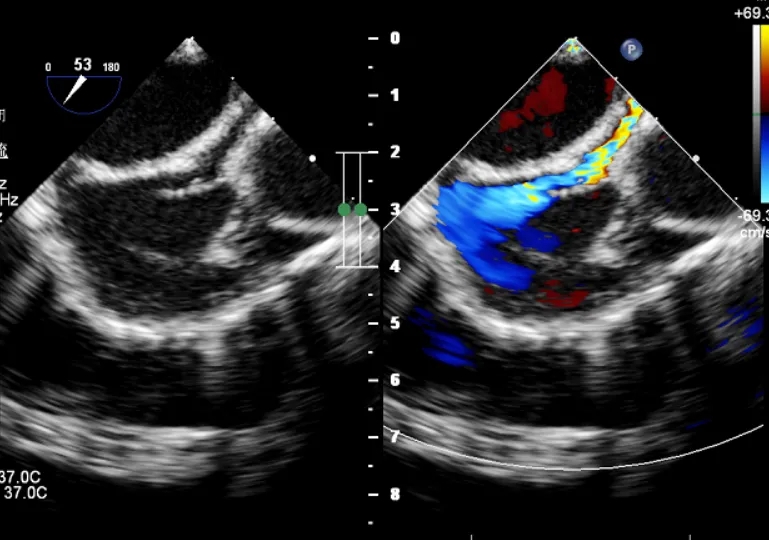

术后超声检查

超声下可见封堵器形态位置正确,未见明显血流通过,封堵器盘面贴合,位置固定

经导管介入治疗CAF因其安全、有效和创伤小的特点,目前已经被广泛使用。考虑本例冠状动脉瘘病变血管直径较粗,采用传统的弹簧圈进行封堵可能会导致锚定不稳或发生持续残余瘘或瘘管再通等风险,而采用传统金属封堵器封堵后易形成血栓造成心肌梗死。因此经术者综合考虑后,最终选择了ABFDQ-II 8规格全降解封堵器进行封堵。全降解封堵器具有良好的柔韧性,植入后能够自适应复杂的冠脉血管结构形态和组织运动,其对称双盘样结构结合专利锁定设计又能有效阻断血液分流,保证封堵稳定。此外,全降解封堵器在术后可逐渐降解,避免了金属封堵器长期存在体内可能引发的血栓风险。术后造影可见瘘管封堵完全,右心房无显影,超声下可见封堵器形态位置良好,未见残余分流,封堵成功。